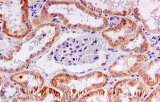

Immunhistochemie (IHC) ist eine histologische Technik, die darauf abzielt, ein Zielprotein im Gewebe zu lokalisieren. Es gibt auch eine abgeleitete Technik, die Immunzytochemie (ICC), die nach dem gleichen Prinzip funktioniert, jedoch ein Zielprotein in isolierten Zellen nachweist.

Das Prinzip der Immunhistochemie beruht auf der Erkennung eines Antigens durch einen spezifischen Antikörper und der Entwicklung dieses Antigen-Antikörper-Komplexes durch eine chemische Reaktion mittels eines Enzyms und seines Substrats. Üblicherweise handelt es sich bei dem Enzym um HRP (Meerrettichperoxidase) oder AP (Alkalische Phosphatase) und deren Substrate AEC und DAB für HRP bzw. NBT/BCIP und Permanent Red für die alkalische Phosphatase.

Es ist möglich, ein einzelnes Protein (Einfachfärbung) oder mehrere Proteine auf demselben Gewebeschnitt (Mehrfachfärbung) zu lokalisieren.